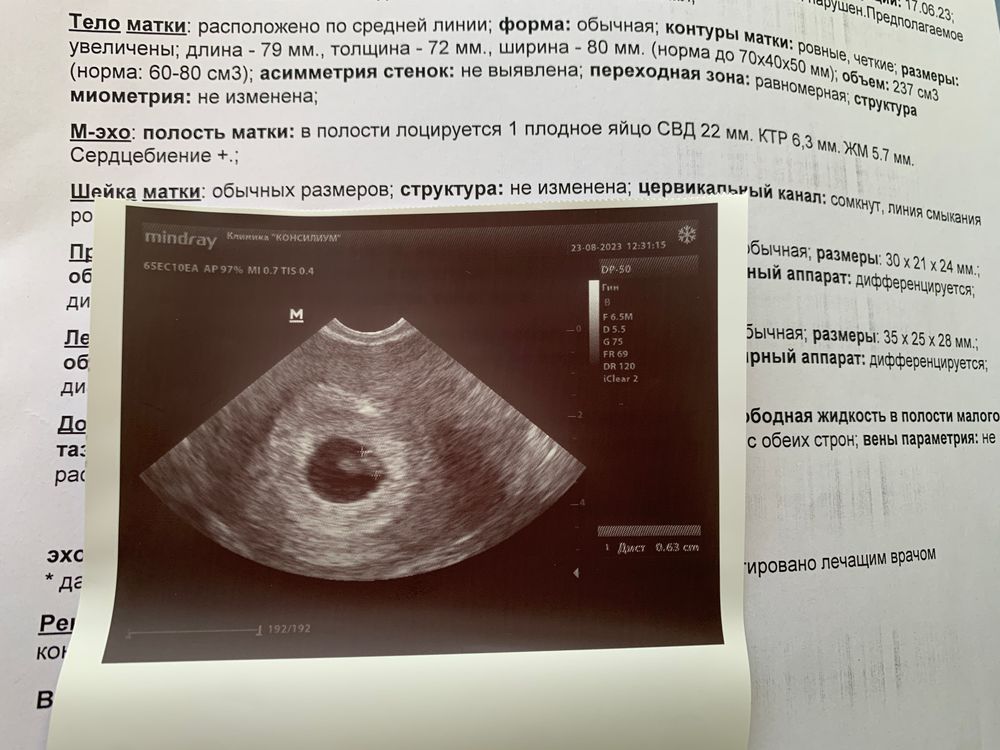

В прошлый понедельник врач на УЗИ увидела только желточный мешочек. Во вторник я сдала ХГЧ, результат был 14000. В среду пошла к другому врачу на УЗИ, та уже разглядела эмбриончика 2 мм, но СБ не было видно.

Вчера, во вторник, сдала снова ХГЧ, результат 39000 пришел. Насторожило, что не сильно быстрый прирост за неделю. Сегодня пошла к своему врачу на УЗИ, она уже увидела эмбриончика 63 мм с сердцебиением. Поставила срок 6 недель (беременность незапланированная, цикл у меня длинный и нерегулярный и своей овуляции раньше не было, так что когда была овуляция я не знаю).